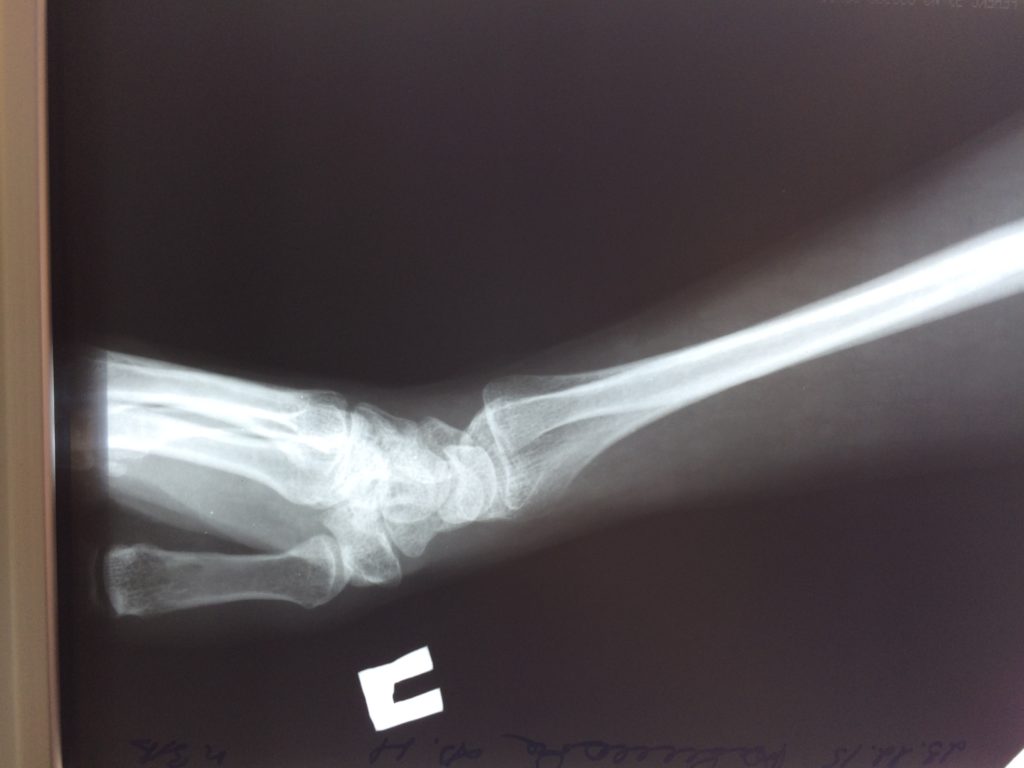

Отдаленные результаты через 6 (шесть) месяцев